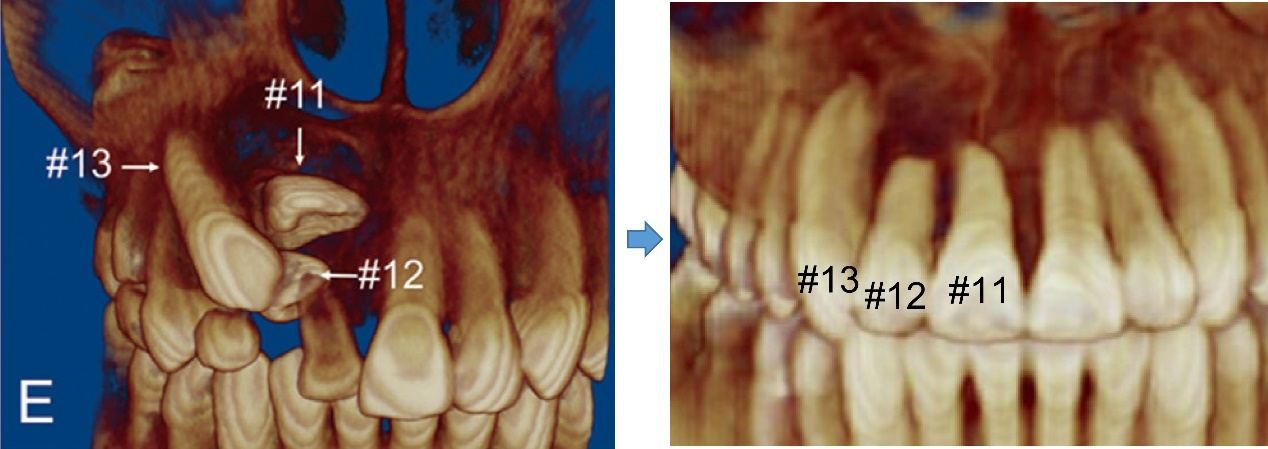

A 11-year-old girl came to our hospital complaining about “missing” front teeth. Radiographs showed that the right maxillary permanent canine, lateral and central incisors were all impacted. Particularly frustrating were the two closely stacked incisors with the roots excursing far away from the right position and embraced in a big cyst. If the incisors could not be drawn and aligned, the girl would have to face a front-teeth-missing adolescence with affected facial esthetics, oral function and self-confidence.

The orthodontic team made a delicate treatment plan after comprehensive examination and analyses. The three impacted teeth were under traction one by one, and the long-distance controlled root tipping was achieved with precise biomechanics. More importantly, a novel crimpable “gate spring”, invented by Prof. Yu Li and Prof. Zhihe Zhao, was used to boost the large-angle root torque movement with high efficiency, playing a pivotal role in perfection of this case.

Now the lucky girl can happily show her bright and confident smile with no embarrassment any longer. With publication of this featured case report, the innovative orthodontic techniques, particularly the self-developed high-efficiency torquing auxiliary “gate spring”, will be applied by more orthodontists around the world to benefit their patients.